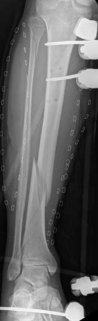

With the articular surface reconstituted, the surgeon's focus shifts to bridging the complex metaphyseal-diaphyseal dissociation. A pre-contoured anatomical locking plate is slid submuscularly or subcutaneously along the diaphysis using a MIPPO technique. The plate is positioned on the anterolateral or medial surface, depending on the preoperative plan and soft tissue constraints.

The distal portion of the plate is secured to the reconstructed articular block. It is imperative that the distal locking screws are placed parallel to the joint space, forming a rigid subchondral raft that supports the articular cartilage. Fluoroscopy is utilized extensively to ensure no screws have penetrated the joint. Once the distal block is secured to the plate, the diaphyseal segment is aligned. Length, alignment, and rotation are restored using manual traction or the femoral distractor. The proximal portion of the plate is then secured to the diaphysis using a combination of non-locking screws (to pull the bone to the plate) and locking screws (to create a fixed-angle construct). The working length of the plate is maximized by leaving several screw holes empty over the zone of comminution, promoting secondary bone healing.